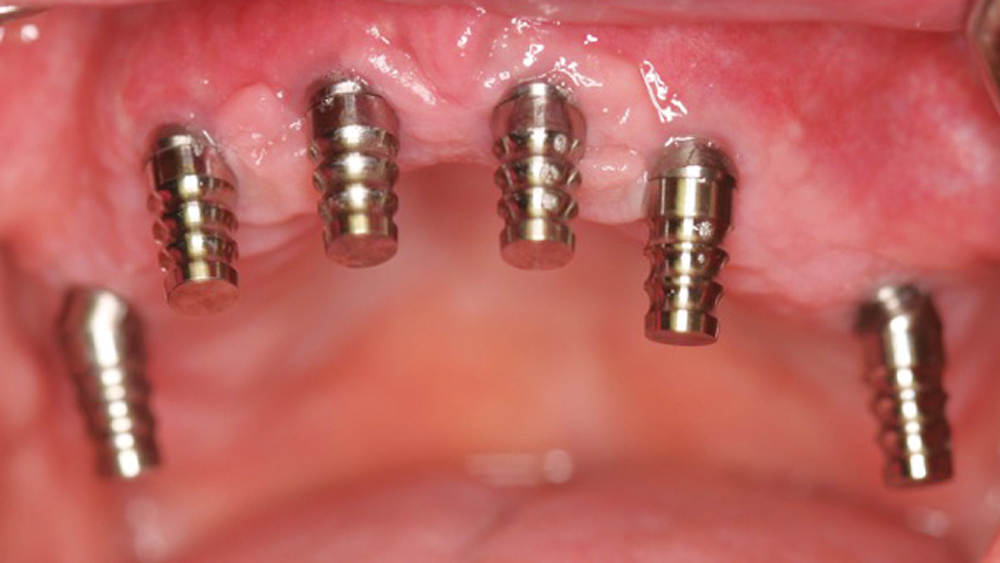

To establish the foundation needed for a screw-retained restoration and avoid fracturing the facial plate, clinicians must position the immediately placed implant against the lingual or palatal wall of the extraction socket. This is one of the reasons I designed the Hahn™ Tapered Implant (Glidewell Direct; Irvine, Calif.) with deep, sharp threads, which enable precise directional control during insertion and prevent the implant from “walking” toward the facial plate as it is threaded into place. This thread design also leads to high primary stability in all bone types, which is essential when performing the extraction with immediate implant placement procedure.1,2

The following case demonstrates how to immediately place implants in full-arch indications. By properly positioning the implants, maximizing primary stability and providing the most durable restoration possible, the short- and long-term needs of the patient are addressed in an efficient, predictable manner.